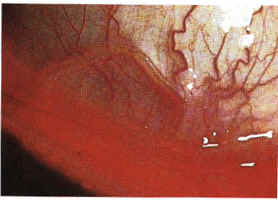

絲蟲病2.羅阿絲蟲病:由羅阿絲蟲寄生於人體皮下組織引起的疾病。流行於西非及蘇丹。學名中Loa一詞系剛果土語,意為“眼蟲”,因該絲蟲的成蟲常移行到眼部,故名。成蟲寄生於人體皮下組織,到處竄行,形成遊走性皮膚腫塊,常見於背、腋、腹股溝、頭皮、眼皮,亦見於眼前房、球結膜等處。雌蟲在移行過程中間歇地產出微絲蚴。微絲蚴具鞘膜,進入血流,呈晝現周期性,夜間則集中於肺部,患者為唯一傳染源。中間寄主為白晝吸血的幾種斑虻。微絲蚴被吸入虻腸中後,移行到其脂肪體內,經7天發育為感染性幼蟲,並移行至口器,於虻叮人時自其口器逸出,經吸血傷口浸入人體。1年後發育為成蟲,此時方引起遊走性腫物(可大如雞蛋,持續數小時至數日)、皮膚瘙癢及蟻行感、結膜炎等症狀。診斷靠血中檢獲微絲蚴或於皮下組織、眼結膜下查獲成蟲。乙胺嗪治療有效。摘出成蟲的手術簡便可靠。

3.盤尾絲蟲病:由盤尾絲蟲寄生於人體皮下組織引起的疾病。流行於非洲中部和墨西哥、南美北部等地。流行病變乃致失明,故本病又稱河盲症。盤尾絲蟲成蟲大於淋巴型絲蟲,寄生於胸、腹、腰、腿、頭部皮下組織,周圍形成纖維包膜,表現為皮下結節,內含2條或更多的成蟲,大小約5~25mm,不痛,局部皮膚瘙癢。微絲蚴無鞘膜,產於皮下結節內,可鑽到結節周圍組織及淋巴管、血管內,但外周血液中很少見,無明顯周期性。成蟲若寄生於眼眶附近,微絲蚴可經淋巴管或微血管移行至眼球,引起角膜、虹膜、脈絡膜、視網膜的炎症,亦可損傷晶狀體、玻璃體,造成視力障礙,甚至失明。傳染源為患者,尚未發現家畜保蟲寄主。傳播媒介及中間寄主為蚋。蚋的口器粗短,不適深刺,吸血時亦吸入大量組織液,微絲蚴隨組織液吸入蚋的消化道內,隨後移行至胸肌,6~7天后發育成感染性幼蟲──絲狀蚴,移行至蚋的下唇,於蚋叮人時浸入人體。有報導感染後40天即出現症狀。本病確診靠皮下結節處表皮活體檢查檢獲微絲蚴。乙胺嗪可殺滅微絲蚴,但應注意過敏反應,對成蟲無效。靜脈注射蘇拉明可殺滅成蟲。皮下結節可用手術摘出。